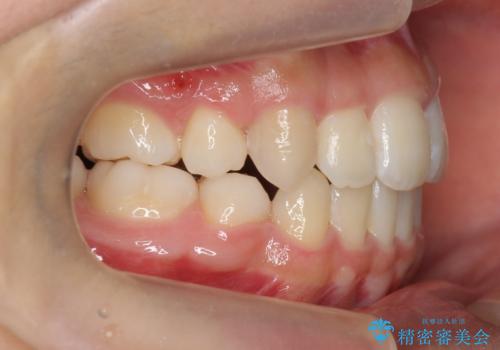

八重歯や、前歯のオープンバイト(開咬)の症状があり、マウスピース(インビザライン)矯正単独では治すのが難しい症状が複合していました。

八重歯や抜歯したスペースの閉鎖をワイヤー矯正で前半行い、治療後半は目立たないインビザラインでかみ合わせを調整しました。

ワイヤー矯正からインビザラインへの変更は、歯磨きも簡単になり、目立たず、さらにワイヤーと併用することで妥協せずしっかり治療結果も出すことができます。